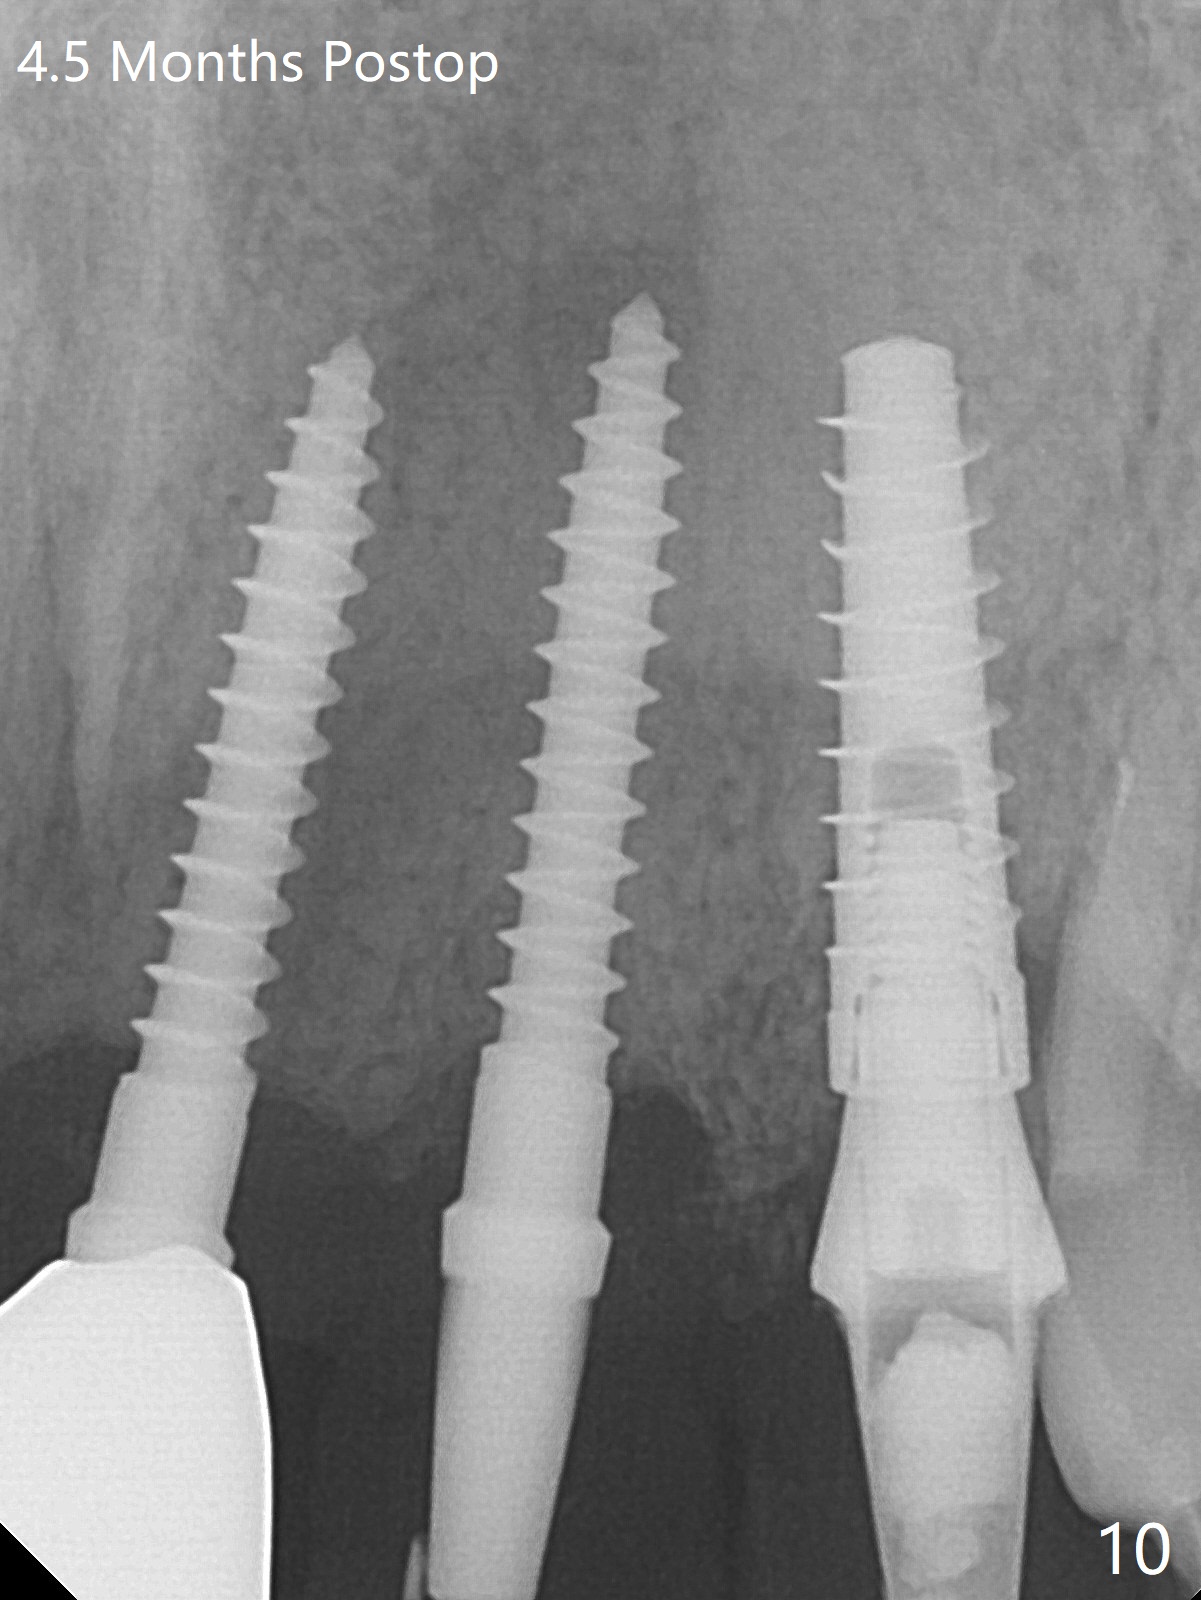

The buccal plate at #10 undergoes atrophy 9 months post immediate implant (Fig.1 *). To prevent the same post-extraction complication at #11, a technique called socket shield is going to be adopted. The buccal portion of the root (Fig.2-6 R, half-moon shaped) remains in place while a 3.5x13 mm implant is placed in the palatal portion of the socket (>50 Ncm). In fact the root is trimmed slightly subcrestal (Fig.6 C). It is assumed that there will be no or minimal bone resorption as long as the periosteum between the buccal plate and the remaining buccal root is not disturbed after tooth removal. After placement of a 4.5x15 degrees A (2mm) angled abutment and Vanilla graft (Fig.7 *), an immediate provisional is fabricated (using a central incisor crown form for #10 because of extra wide space of #11, Fig.8). There is no buccal plate atrophy at the canine 11 days postop (Fig.9). There is smooth transition from the grafted bone to the native bone 4.5 months postop (Fig.10). The buccal plate remains non-atrophic at the canine 4.5 months postop (Fig.11,12). CT taken 1 month post cementation shows that the implants at #10 and 11 are placed somewhat lingually (Fig.13,14 L (*: socket shield)). Gingival swelling is noted (Fig.15 *) with +Bleeding On Probing (^) 8 months post cementation (at the time of #21/24 impression). It appears that the socket shield (Fig.16 S) causes infection and loss of bone graft (*). The shield will be removed with an oblique accessory incision to save the papilla between #10 and 11 (Fig.17 black line). Prepare PRF for sticky bone (x1).